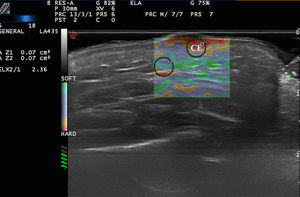

Benign Skin Tumors and Neck MassesAlthough benign subcutaneous tumors have a recognizable appearance in B-mode ultrasound,21 in doubtful cases elastography could play a useful role in the differential diagnosis.

In a study by Bhatia et al.,22 52 non-nodal neck masses were evaluated using real-time qualitative ultrasound elastography. The diagnosis of the lesions was later corroborated by cytology and histology. The lesions were evaluated semiquantitatively on a scale of 0 to 3, where 0 was completely soft and 3 was completely stiff. Lipomas were less stiff than other types of lesions, most of which were cysts, malformations, and neurogenic tumors (Fig. 4). In an extension of the study, SWE was used to assess malignant and benign neck tumors.23 The mean stiffness of the malignant tumors (226.4kPa) was higher than that of the benign lesions (28.3kPa) and the difference was statistically significant. With a cut-off of 174.4kPa, sensitivity of 83.3% and specificity of 97.5% were achieved in the differentiation of benign and malignant lesions. The authors noted that all tumors were correctly diagnosed with conventional ultrasound and that elastography would not have altered the treatment, but they argued that less experienced operators could find the technique helpful in the diagnosis of neck lesions.

Park et al.24 used elastography to differentiate inflamed and unruptured epidermal cysts (Fig. 4, B), the latter being stiffer than the former.